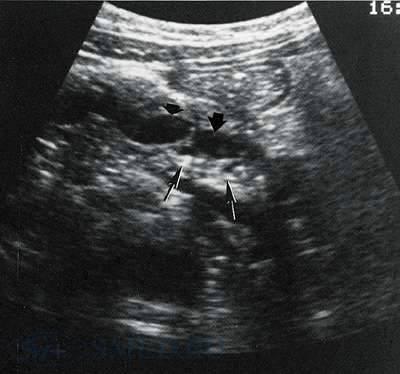

УЗИ относится к необходимым исследованиям при подозрении на патологический процесс в поджелудочной железе.

Обычно для определения нижней границы тела и хвоста железы ориентиром служит селезеночная вена. Границы головки определяются соотносительно двенадцатиперстной кишки. Исследование можно считать полноценным, если визуализирован проток поджелудочной железы. Обычно это удается у 70-80% обследованных.

В пользу хронического панкреатита наиболее часто свидетельствует увеличение эхогенной плотности железы, появление неровности контуров и изменение размеров. У части больных отмечается уменьшение железы, выявляются кальцинаты и деформации протоков железы.

УЗИ выявляет четкие изменения в железе у 60-70% больных

хроническим панкреатитом, поэтому метод не применим для исключения заболевания.

Рис. 2. УЗ-исследование поджелудочной железы при хроническом панкреатите. Тонкими стрелками указаны кальцификаты, а толстыми стрелками - расширенный и сегментированный проток поджелудочной железы.